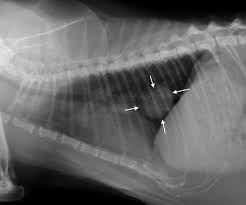

Lung Cancer In Cats Causes Symptoms Treatment All About Cats from allaboutcats.com A number of studies have indicated that animals, too, face health risks when exposed to the toxins in second hand smoke, from respiratory problems, allergies and even nasal and lung cancer in dogs and lymphoma in cats. More on secondhand smoke and lung cancer: Animals are subjected to the effects of secondhand smoke as are humans. Julian's cat care, in dearborn, mich. You can help lower your risk of lung cancer by staying away from secondhand smoke, diesel exhaust, and other air pollution. Research shows just how dangerous second and third hand smoke is to the animals who live with us. A number of studies have indicated that animals, too, face health risks when exposed to the toxins in second hand smoke, from respiratory problems, allergies and even nasal and lung cancer in dogs and lymphoma in cats. Both types of lung cancer primarily affect cats that are over ten years of age.

You should get your home tested for radon and take steps to lower the radon level if it is high. Common cancers with the potential to spread to the lungs include oral, mammary, liver and bone. In the united states, at least 30 percent of all cancer deaths each year are caused by cigarette smoking and secondhand smoke exposure. Animals are subjected to the effects of secondhand smoke as are humans. Cats and secondhand smoke cats are more prone to develop cancers of the mouth and lymph nodes because of secondhand smoke. Secondary (metastatic) lung cancer is the most common type of cancer to affect cats. Lymphoma, lung cancer, and oral cancer (from licking smoke residue) rates have both been shown to be higher in cats exposed to smoke routinely. Approximately 7,3301 cases of lung cancer are caused by secondhand smoke each year. And if you already have asthma, it may get worse. Secondhand smoke and cats although we know less about the effects of secondhand smoke, or environmental tobacco exposure, in cats, what we do know is concerning. Lung cancer isn't the only risk. You're also more likely to get heart disease and stroke. Cats (pets) can have other cancer t.

Second Hand Smoke And Cancer Risk For Pets Petmd from www.petmd.com Animals are subjected to the effects of secondhand smoke as are humans. Metastatic lung tumors are a secondary type of lung cancer that originally forms in another part of the body and spread to the lungs. In other words, again most patients with lung cancer are smokers and passive smoking. The health risks associated with inhaling secondhand smoke have proved to be just as worrisome for cats as they are for people. A number of studies have indicated that animals, too, face health risks when exposed to the toxins in second hand smoke, from respiratory problems, allergies and even nasal and lung cancer in dogs and lymphoma in cats. Cancer develops elsewhere in the body and spreads to the lungs via the bloodstream. That risk increases with prolonged exposure. In the united states, at least 30 percent of all cancer deaths each year are caused by cigarette smoking and secondhand smoke exposure.